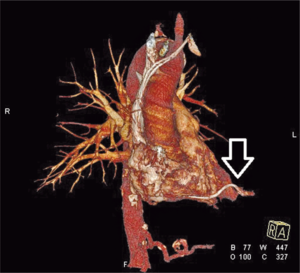

Perforacja prawej komory lub prawego przedsionka w czasie implantacji układu stymulującego lub kardiowertera-defibrylatora (implantable cardioverter-defibrillator, ICD) są stosunkowo rzadkie. Należy zauważyć, że mogą one występować wcześnie po zabiegu lub po upływie kilku godzin lub dni (do 30 dni – subacute perforation) [7-9]. Perforacja może być spowodowana przebiciem ściany prawej komory lub przedsionka przez elektrodę. Częstym mechanizmem jest penetracja ściany serca przez element mocujący elektrodę (active fixation lead). Ze względu na niewielkie uszkodzenie ściany serca krwawienie do worka osierdziowego nie jest nasilone, więc objawy pojawiają się po upływie dłuższego czasu od zabiegu. Przebieg kliniczny może przypominać ostre zapalenie osierdzia. Wysięk w worku osierdziowym może występować okresowo, może też nie być obecny (ryc. 1). Postępowanie obejmuje drenaż osierdzia i zmianę pozycji elektrody pod kontrolą radiologiczną w zabezpieczeniu kardiochirurgicznym (np. w warunkach sali hybrydowej) [1,4,7,8].